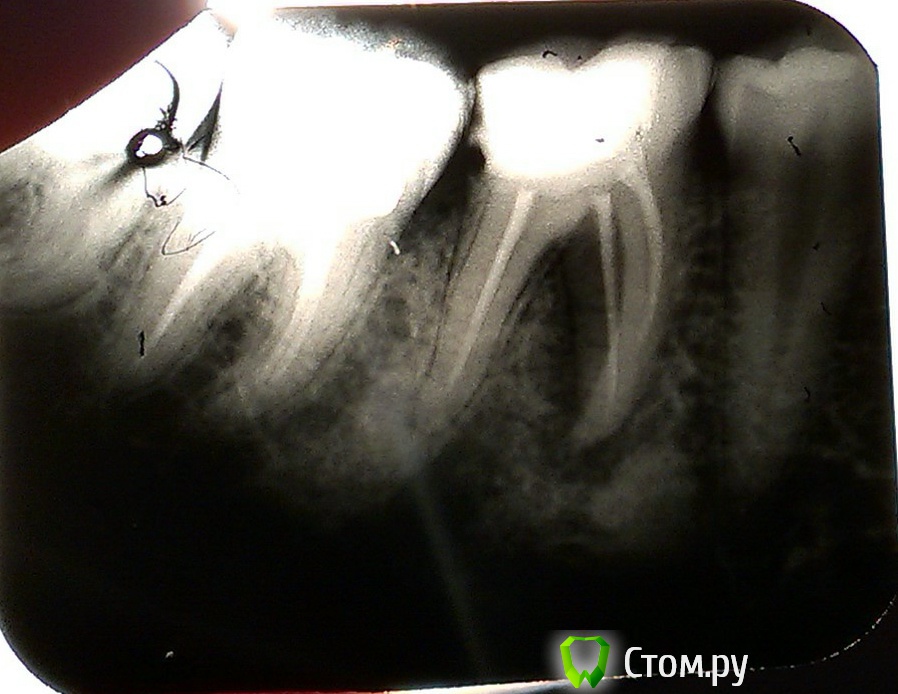

Добрый день, уважаемые стоматологи! Мне 30 лет. Неделю назад отекла  десна со стороны щеки возле 6 зуба внизу слева. Зуб депульпирован,если не ошибаюсь, в 2010 г. Перелечен в октябре 2013 г., так как откололся кусочек зуба. Через время после этого заметила, что появилась боль при постукивании. Была у 4 врачей. Двое сказали,что нужно сделать уколы линкомицина в десну, это снимет воспаление и пока можно так ходить,а затем все равно удалить через какое-то время, может и несколько лет. Только 4 доктор сказала, что зуб кандидат на удаление, уколы в десну ни в коем случае не делать. На снимке видно разрежение кости (вроде бы так?) и при осмотре зонд вошел до корня (что это значит,я не совсем поняла). Доктор предложила попробовать гемисекцию, либо удалить зуб,чтобы он не был очагом инфекции. Перед этой операцией назначила Цифран-СТ, брустан и горячие содовые ванночки. Если это не снимет воспаление, то удалять. Зуб не болит, иногда поднывает десна. Я кормящая мамочка. Было сказано приостановить кормление на 10 дней, но это не так просто сделать. В общем пока я ничего из лекарств не пью, делаю только ванночки. Скажите, пожалуйста, зуб действительно уже не спасти? Почти 2 месяца назад я уже удалила 6 справа. Там была гранулема. Заранее спасибо!!!